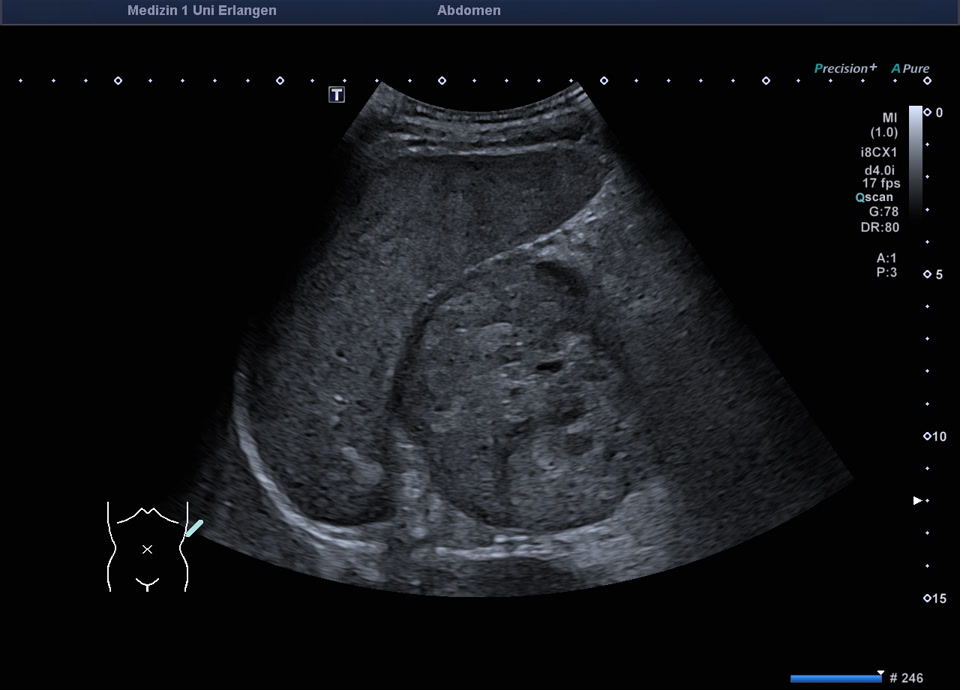

47-year-old patient presents to the emergency department with flank pain. Ultrasound shows a large, inhomogeneous, sharply defined mass in the left adrenal gland. A blood sample (including metanephrines) and a puncture (endosonographic access) are initiated for further clarification. Histologically adrenal cancer